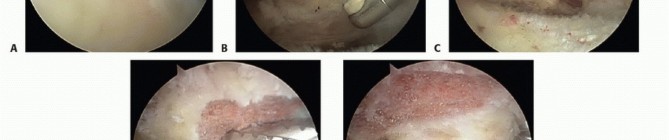

The electrocautery device is used to peel the coracoacromial ligament from the undersurface of the acromion and completely excise the remaining ligament stump. A complete resection of the coracoacromial ligament is confirmed when the undersurface of the deltoid is visualized as it drapes over the acromial edge(TECH FIG 2C). Anterior acromioplasty is performed with a 5.5-mm burr via the lateral portal. Resection begins in the anterolateral corner of the acromion. The desired depth of resection, estimated from the preoperative films, is obtained by measuring with the diameter of the burr(TECH FIG 2D).

TECH FIG 2 • A. Arthroscopic bursectomy. The bursa overlying the tendinous portion of the rotator cuff must be thoroughly resected to evaluate the tendons for bursal-side rotator cuff tear. B. Soft tissue on the undersurface of the acromion is denuded with a radiofrequency electrocautery. Removing the soft tissue will expose the bony undersurface of the acromion and facilitate acromioplasty by the burr's cutting flutes. C. The acromial spur is now completely visualized. The coracoacromial (CA) ligament must be completely resected from the anterolateral acromion. Failure to do so may result in residual impingement by the CA ligament. Visualization of the undersurface fibers of the deltoid indicates a complete CA ligament resection. D. The acromioplasty begins at the far anterolateral tip of the acromion. The burr's diameter, usually 5 to 6 mm, is used to assess the initial depth of the acromial resection. The acromioplasty proceeds in 5- to 6-mm strips from anterior to posterior and lateral to medial. E. Completed acromioplasty. The undersurface of the acromion is converted to a type I morphology. Any residual ridges or rough edges can be safely smoothed with the burr in the reverse cutting position. F. View of the acromioplasty from the lateral portal. At the procedure's completion, the arthroscope should be placed in the lateral portal to assess the acromion for any residual downslope or unresected bone. The AC joint is also well visualized from this portal and may be resected or coplaned via the anterior portal. G. Coplaning of the AC joint. The posterior or lateral portal is used for arthroscopic visualization. Coplaning is performed with the burr in the anterior or lateral portal. This depth of resection is achieved anteriorly from the anterolateral corner of the acromion to the medial acromial facet of the AC joint. The depth of resection is then progressively thinned posteriorly to the midportion of the acromion such that there is a smooth zone of transition from the anterior to the midportion of the acromion(TECH FIG 2E).

Any ridges or rough edges may be smoothed with the burr in the “reverse cutting” position. The reverse position provides a much less aggressive bone resection, which is ideal for smoothing the soft cancellous undersurface exposed following acromioplasty. The arthroscope is placed in the lateral portal to check the adequacy of resection(TECH FIG 2F). Any residual unresected acromion or impinging osteophytes from the undersurface of the AC joint should be resected. Radiofrequency electrocautery should be used to resect the highly vascular soft tissue on the undersurface of the AC joint. From the anterior or lateral portal, the 5.5-mm burr is used to coplane the distal portion of the clavicle flush with the acromion(TECH FIG 2G).

TECH FIG 3 • Completed acromioplasty via the “cutting block” technique. The acromion is viewed from the lateral portal while the burr is used to approach the acromion from the posterior portal. The burr sits flush with the undersurface of the acromion, indicating a type I acromial morphology. Decompression for Symptomatic Os Acromiale The arthroscope is introduced posteriorly and bursectomy is performed as previously described. The mesoacromiale site is identified(TECH FIG 4A). Direct pressure on the superior aspect of the anterior acromion confirms instability at the mesoacromiale junction. A 5.5-mm burr is introduced into the lateral portal. Beginning anteriorly, bone is carefully resected. Preserving anterior fibers of the deltoid, the coracoacromial ligament, and the periosteum of the acromion superiorly are important as to not destabilize the fragment. The resection should proceed posterior to the nonunion site and medial to the AC joint. The os acromiale should be removed in nearly its entirety, leaving just a thin cortical shell to preserve the deltoid attachment(TECH FIG 4B).

TECH FIG 4 • A. Arthroscopic view of an unstable mesoacromiale. B. View of the remaining cortical shell